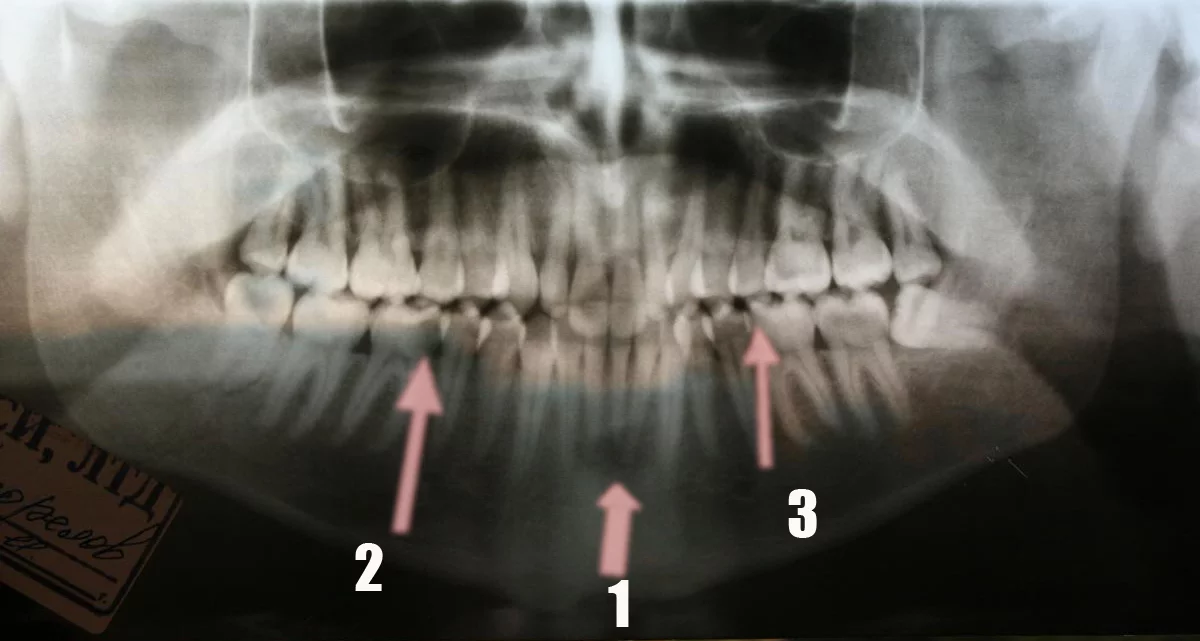

-Перелом угла нижней челюсти справа.

-Есть еще место, которое требует уточнения, это затемнение в области верхушек нижних резцов. Возможно неполный вывих зубов, возможно, поэтому это место было более болезненным.

-Еще на снимке видна кариозная полость в первом моляре на нижней челюсти справа («шестерка»).

-На приеме у стоматолога надо проверить такой же зуб слева.

-Про зуб мудрости на нижней челюсти слева Вам не могли не сказать, хирурги любят об этом говорить.

1. затемнение в области верхушек корней нижних резцов

2. кариозная полость большого размера

3. кариозная полость ?

Хорошо когда есть возможность смотреть на рентгенограмму и проверять в полости рта…